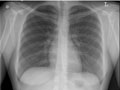

Los pulmones tienen un aspecto normal en cuanto al tamaño y a la forma, y el tejido de los pulmones tiene un aspecto normal. No pueden observarse crecimientos ni otras masas dentro de los pulmones. Los espacios pleurales (los espacios que rodean los pulmones) también tienen un aspecto normal. Vea una radiografía de pecho normal.

El corazón tiene un aspecto normal en cuanto al tamaño y a la forma, y el tejido cardíaco tiene un aspecto normal. Los vasos sanguíneos que van al corazón y que salen de este también son normales en cuanto al tamaño, a la forma y a la apariencia.

Los huesos, incluidas la columna vertebral y las costillas, tienen un aspecto normal.

El diafragma tiene un aspecto normal en cuanto a la forma y a la ubicación.

No se observa una acumulación anormal de líquido o aire; tampoco se observan objetos extraños.